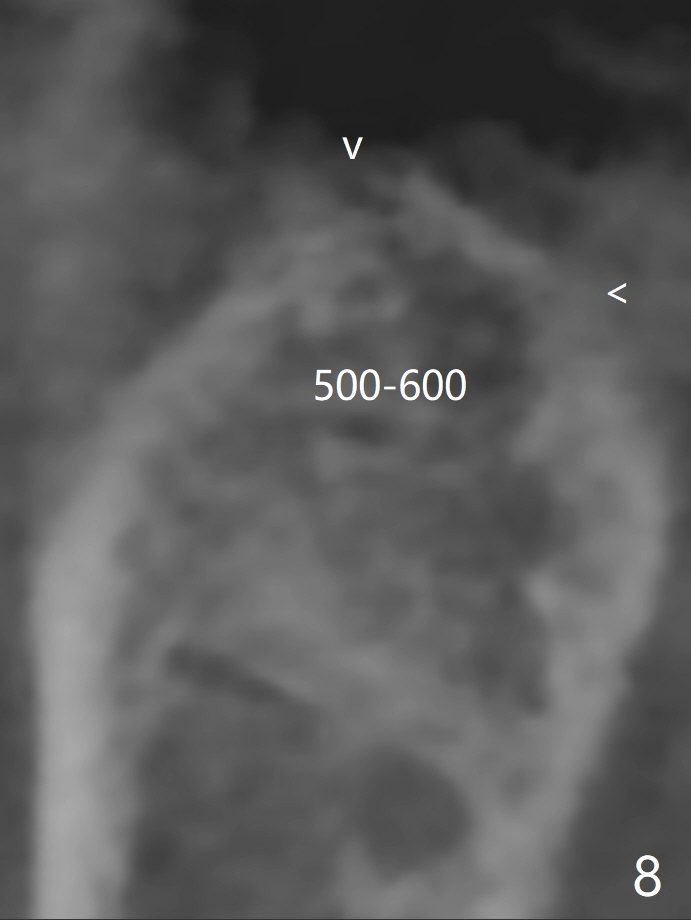

A 61-year-old woman with history of bruxism returns to clinic with chief complaint "I cannot chew bottom right. Top left has had pain and swelling before". Exam shows loose FPD at #31 (Fig.1) and necrosis of #14 (Fig.2). When the FPD is sectioned, the tooth #31 is found to have subgingival caries, filled with IRM (Fig.3). CT shows large PARL around MB and P roots of the tooth #14 (Fig.4), the fractured distal root of the tooth #19 with the low buccal plate (Fig.5) and a 5x10 mm implant being able to be placed at #30 (Fig.6). The crestal cortex (Fig.7 arrowheads) is thin in the edentulous area for several decades. The bone density is low (Fig.8, underprep). To place an implant over the pointed ridge, it should be trimmed prior to osteotomy (Fig.9). The bone loss associated with the fractured distal root is severe at #19 (Fig.10). After removal of the mesial root (Fig.11: 1), perform distal socket shield (2).